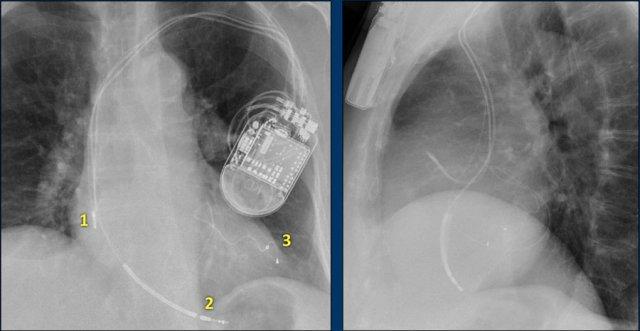

Các phát hiện bao gồm:

- Hai điện cực thượng tâm mạc kết nối với máy tạo nhịp

- ICD

- Hai điện cực đến mỏm thất phải

- Một điện cực chứa hai cuộn sốc điện

- Van ba lá (mũi tên)

- Van hai lá

Đây là bệnh nhân có ICD với một điện cực và hai cuộn sốc điện.

Có thể thấy điện cực lưu lại của máy tạo nhịp cũ đã được tháo bỏ.

Nhiều bệnh nhân có điện cực máy tạo nhịp nội tâm mạc được để lại sau khi tháo bộ phát xung.

Tính an toàn của MRI ở bệnh nhân có điện cực máy tạo nhịp nội tâm mạc lưu lại cho đến nay vẫn chưa được nghiên cứu một cách hệ thống.

Tuy nhiên, do nguy cơ tiềm ẩn khi các điện cực này có thể hoạt động như “ăng-ten” gây nóng đáng kể – không khuyến cáo chụp MRI cho những bệnh nhân này (tài liệu tham khảo).